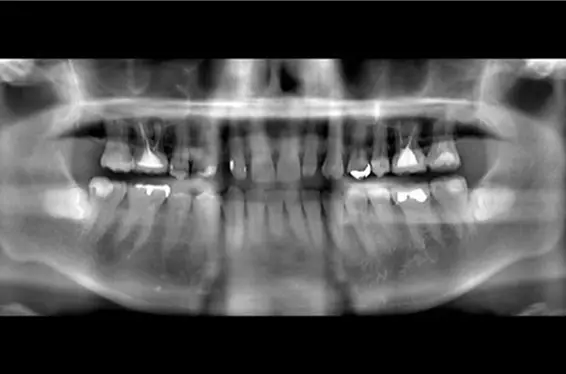

インプラントbefore after画像

• 費用:67万円

• 治療期間:8か月

• 治療内容:右上1、左上、歯根の破折により抜歯。大幅に骨か吸収していたために、1回目骨造成(こつぞうせい)(GBR)手術。4か月後、インプラント埋入手術。右上1番を支台とした、右上1にインプラント埋入,右上1支台,右上1,2のジルコニアインプラントブリッジ